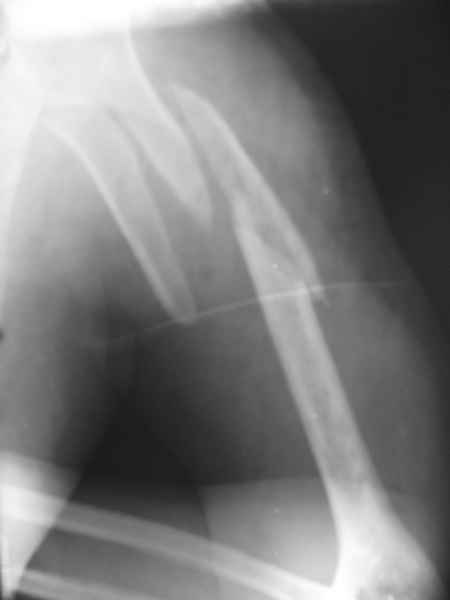

Кроме интрамедуллярного остеосинтеза, имеются другие варианты фиксации, наружный фиксатор и например здесь перелом плеча с повреждением нерва леченный открытым методом. Применен задний доступ с инспекцией нерва, межфрагментарная компрессия, фиксация узкой пластиной 4.5 мм.

Коллеги.

Для ознакомления